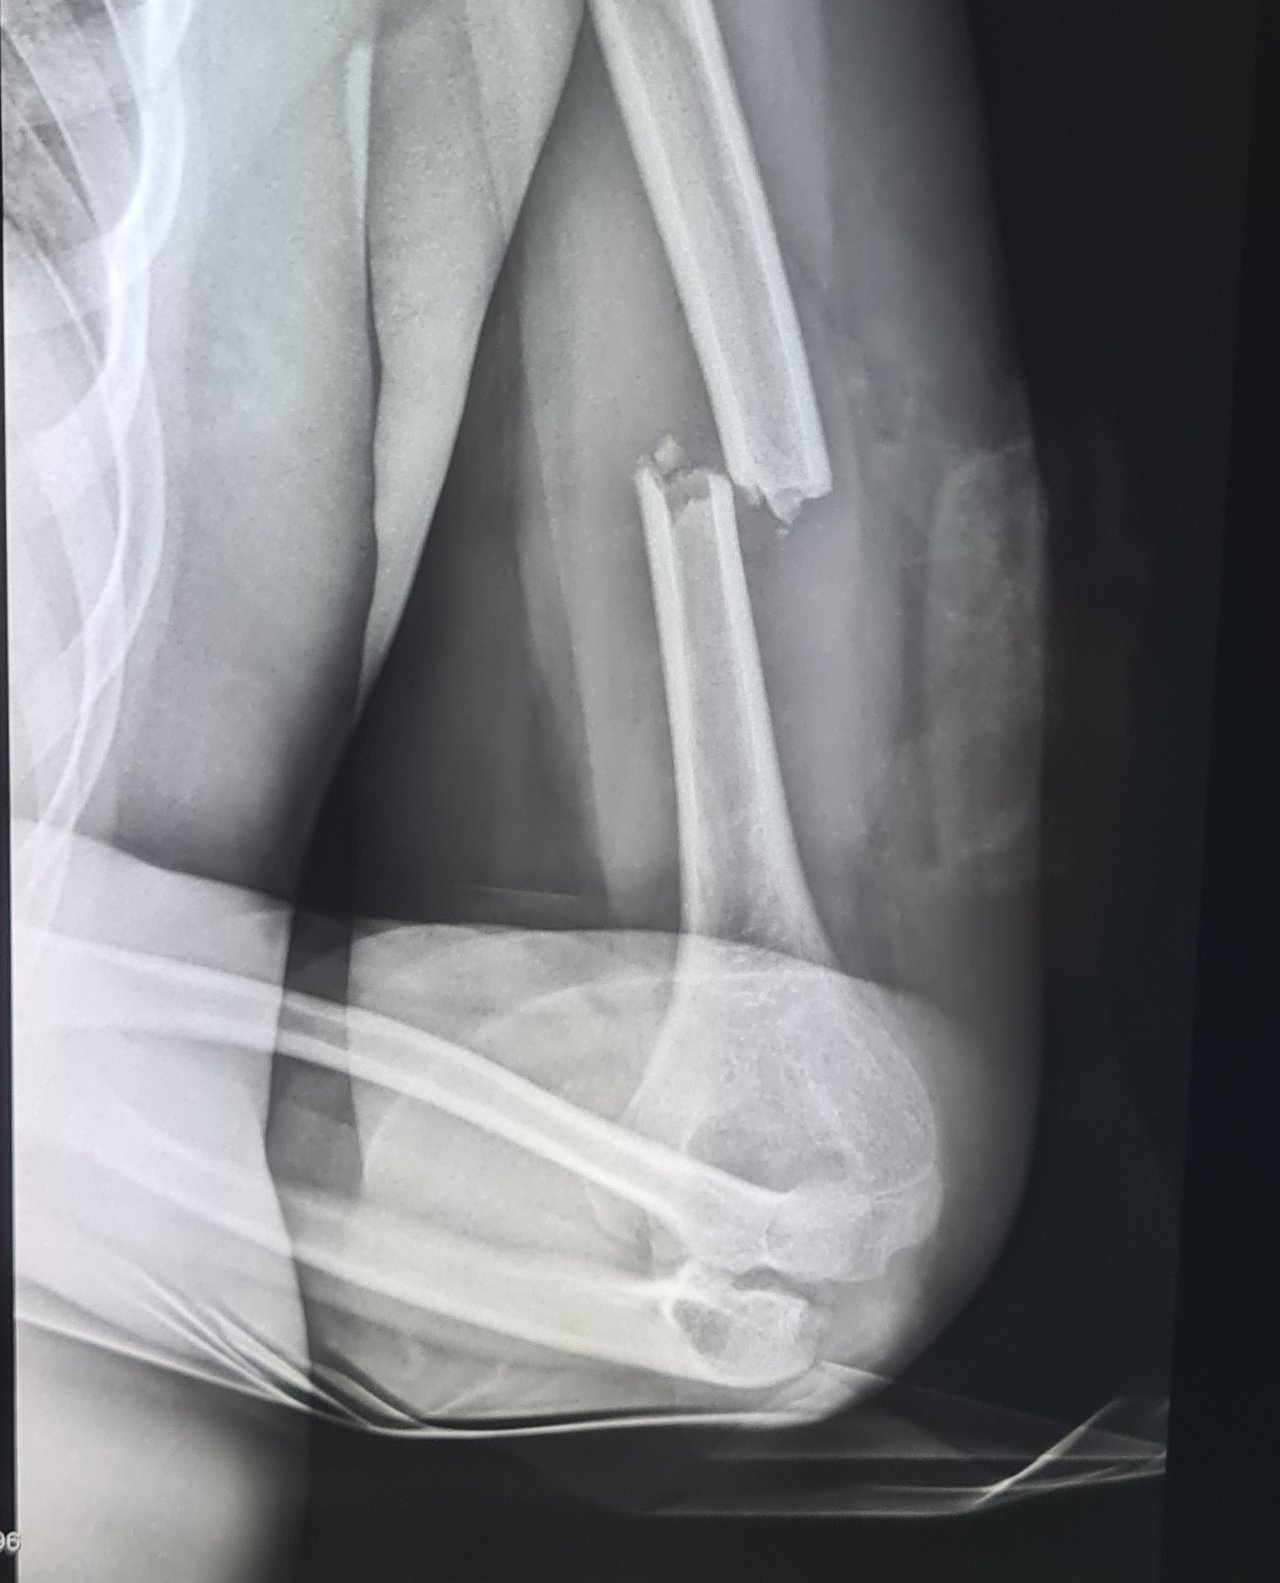

Milyen típusú csont- vagy fejsérülésekkel találkozik leggyakrabban e-rolleres gyermekbaleseteknél?

Dr. Bóta Balázs: Elektromos rollerezés során leggyakoribb a fejsérülés, agyrázkódás, de akár fatális kimenetelű koponyasérülés is előfordul, különösen bukósisak használata nélkül. Az ügyeletekben különböző végtagsérülések sokaságával találkozunk az e-rolleres eleséseket követően. Főleg a felső végtagokon, csukló-, alkar-, könyöktáji, nagy elmozdulással járó, akár nyílt törésekkel, amelyek műtéti ellátást igényelnek. Az alsó végtag sérülései valamelyest ritkábbak. Tompa hasi, mellkasi traumákkal is találkozunk gyermekkorban, eleséskor az e-roller kormánya beleáll a gyerekek hasába, mellkasába amely lép-, máj- és vesesérülést is okozhat. Ez pedig életveszélyes belső vérzést eredményezhet, amely vérátömlesztést, vagy akár sürgős életmentő műtétet tehet szükségessé. Idén nyáron volt olyan betegünk, aki elvesztette az egyik veséjét elektromos rolleres baleset következtében.

Dr. Bóta Balázs: Az e-rolleres balesetek gyógyulási ideje hosszabb, mint például egy sima rollerrel való elesést követő elmozdulás nélküli csuklótáji törés esetében. A hosszabb gyógyulási idő tovább tartó és komplexebb rehabilitációval jár: intenzív gyógytorna, fizikoterápia, hegkezelés. Sajnos, előfordul az is, hogy egy súlyos e-rolleres sérülést, mint a darabos könyöktáji törés esetében, nem sikerül elérni a teljes mozgástartományt és maradandó mozgáskorlátozottság marad vissza. Vagy a korábban említett vese elvesztése miatt a sérült nefrológiai gondozásra szorul akár egy életen át.